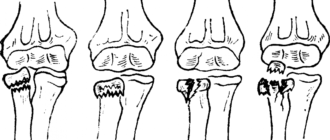

Внутрисуставный перелом головки лучевой кости

Лечение и восстановление локтя после перелома головки лучевой кости Перелом головки лучевой кости локтя,